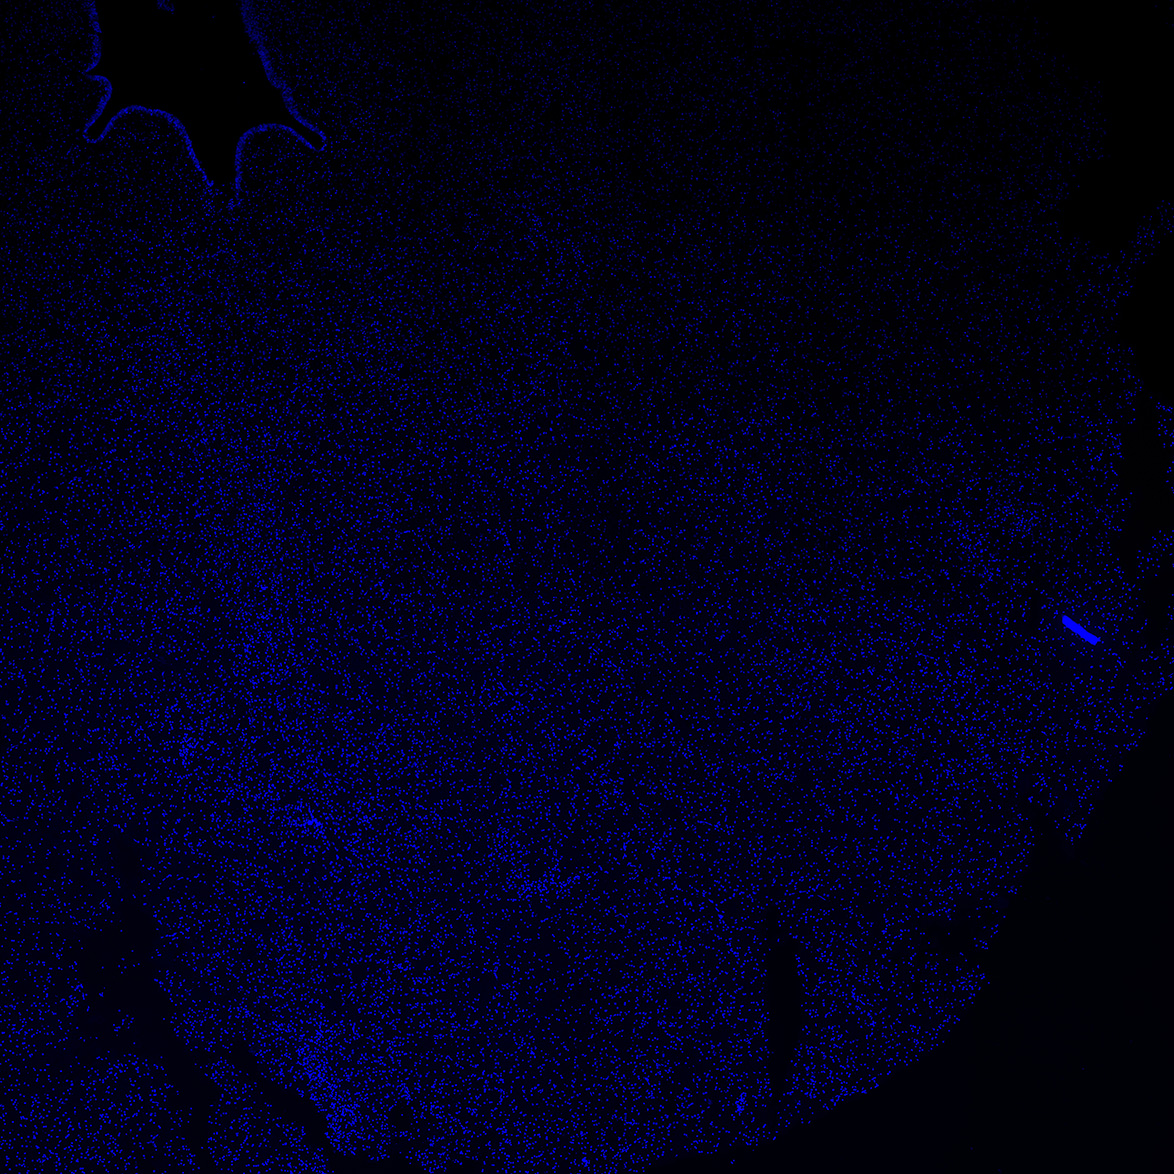

DAPI

6PCW human midbrain